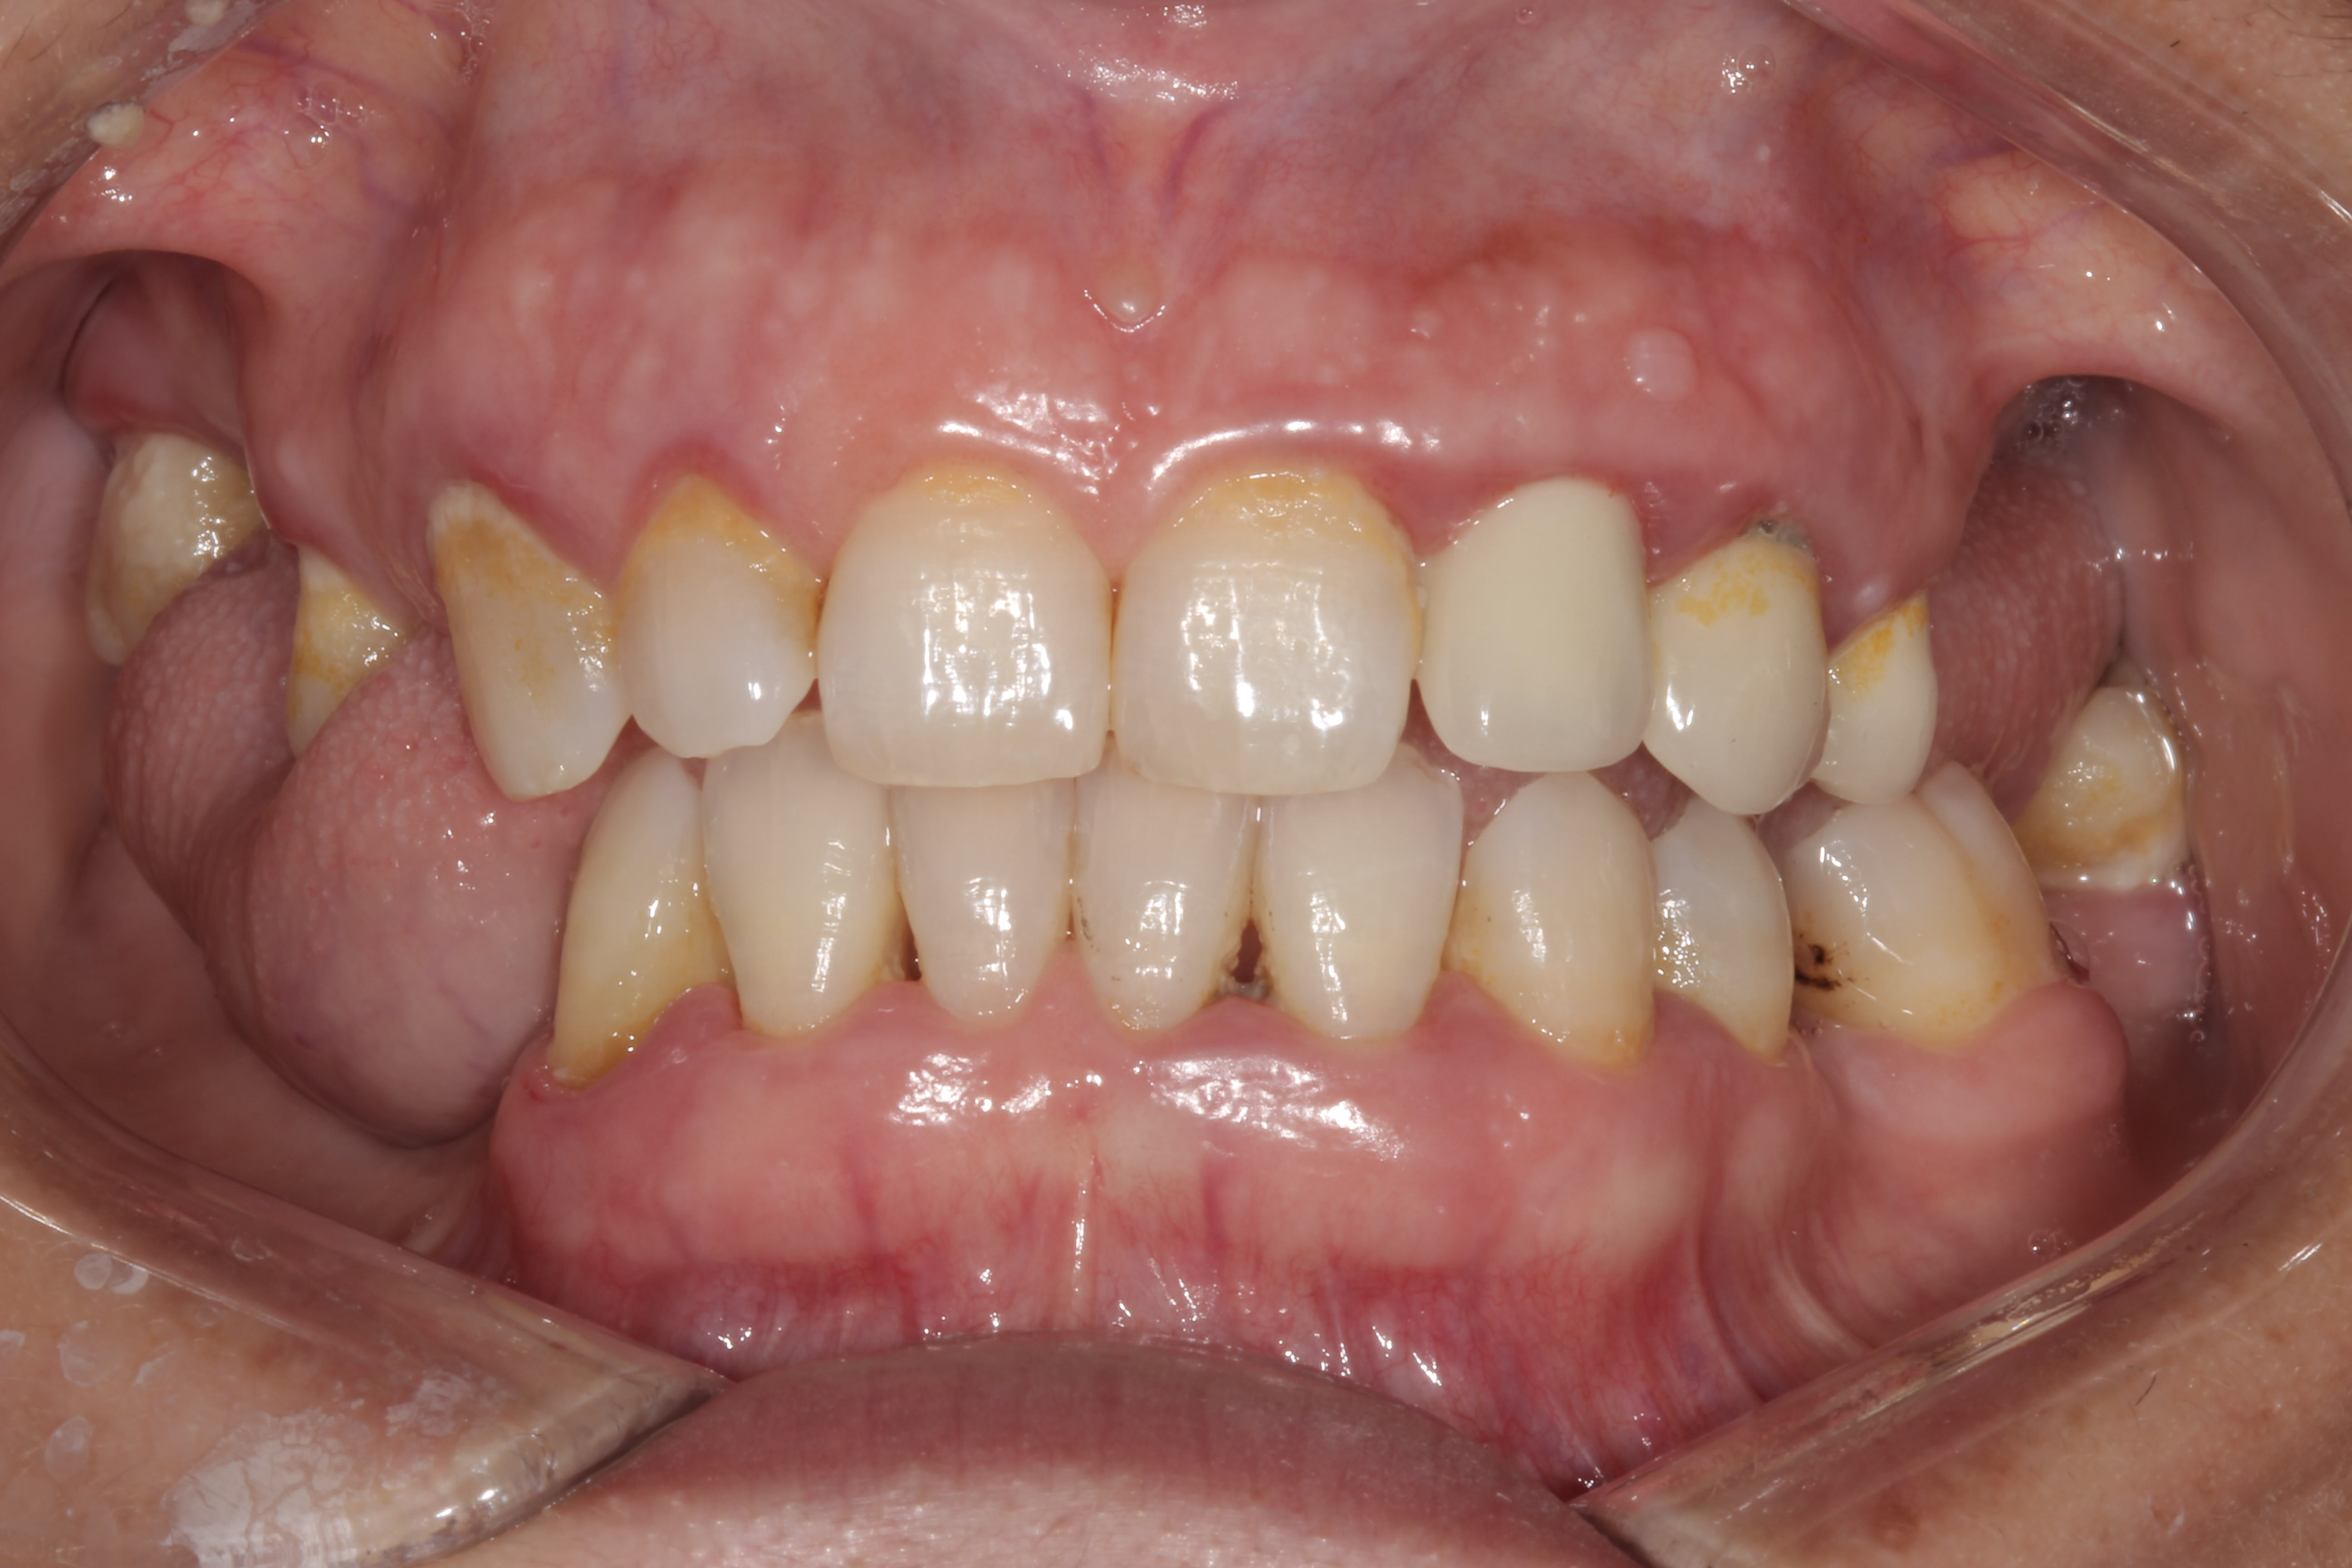

Voici Madame. le changement entre les deux photos c' est le surf et la motivation . Oui, oui, elle est au courant qu' elle doit ameliorer le brossage derriere, mais elle est motivée, passe les brossettes, avec des patients comme ca c' est un plaisir d' aller bosser, mais OK, c' est de loin pas le cas avec la plupart des patients.

1 2 hpmqzd - Eugenol

2 2 vmdus3 - Eugenol